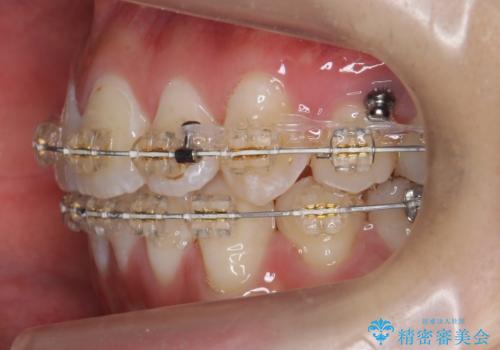

- 矯正装置

- 審美装置

上下の小臼歯を抜歯しています。

矯正用インプラントアンカーを使用してしっかり前歯を下げたため、口元が大きく改善しています。